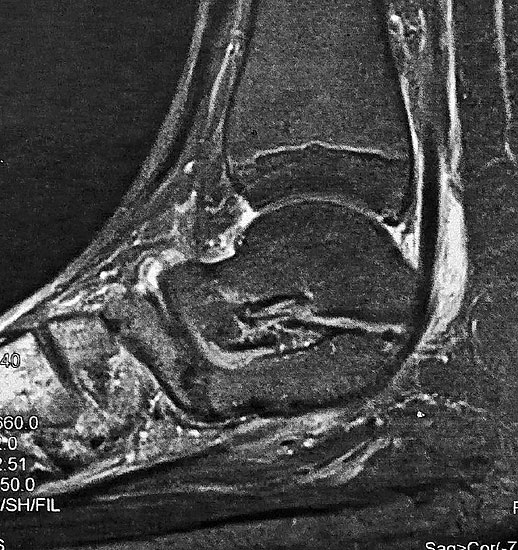

Z.n. Distorsion des Fußes mit „Ruptur“ der (vorbestehenden) talocalcanearen Coalitio. Die Wassereinlagerung in den an die Coalitio angrenzenden knöchernen Bezirken ist im MRT gut zu erkennen. Nach monatelangen Beschwerden spontane Besserung.

Abbildung 1

• Anhaltende Schmerzen nach vermeintlichen oder tatsächlichen Distorsionen („Aktivierung“ der Coalitio, vgl. Abb. 1)